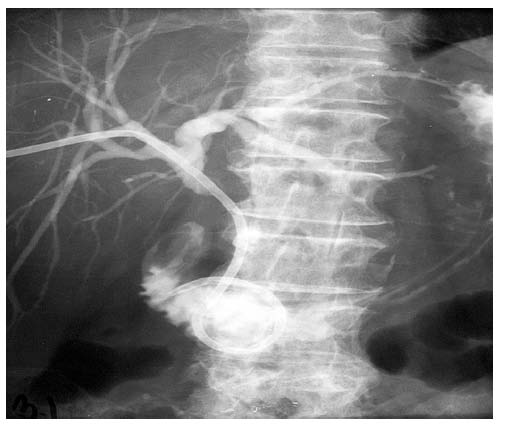

Provedená zevně-vnitřní drenáž žlučových cest u pacienta s maligní stenosou